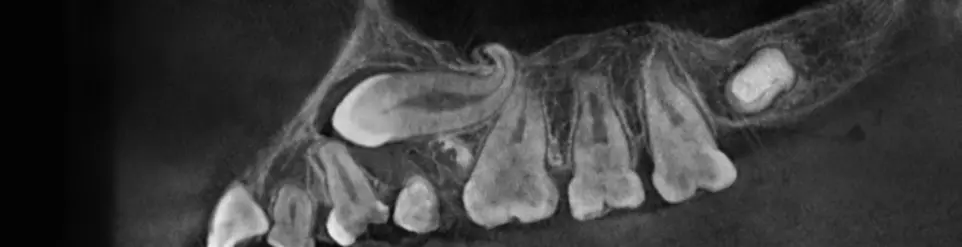

TOMOGRAFÍA DE DIENT​ES RETENIDO

Se da en casos de dientes que no completaron su proceso de erupció​n y su ubicación es compleja.